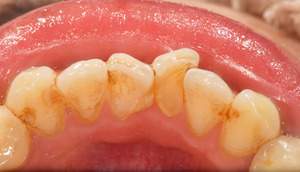

歯石除去

治療前

治療後

| 年齢 | 25歳・男性 |

| 主訴 | 歯石をとりたい・検診 |

| 治療内容 | 各種検査・歯石除去 |

| 治療期間 | 60分 |

| 費用 | 初診料3,000〜4,000円前後 +歯石除去約1,000円 |

| リスク・副作用 | ・処置後に歯がしみることがあります。 ・歯と歯の間に隙間ができるので、息が漏れ発音しにくいと感じることがあります。 ・歯ぐきの炎症が軽減すると歯ぐきが引き締まり、歯が長く見えることがあります。 |

| 担当者所見 | 前歯の裏側にすぐに歯石が溜まってしまいザラザラして気になるとご相談いただいたので適切な歯ブラシの当て方とフロスの通し方をお伝えさせて頂きました。 |